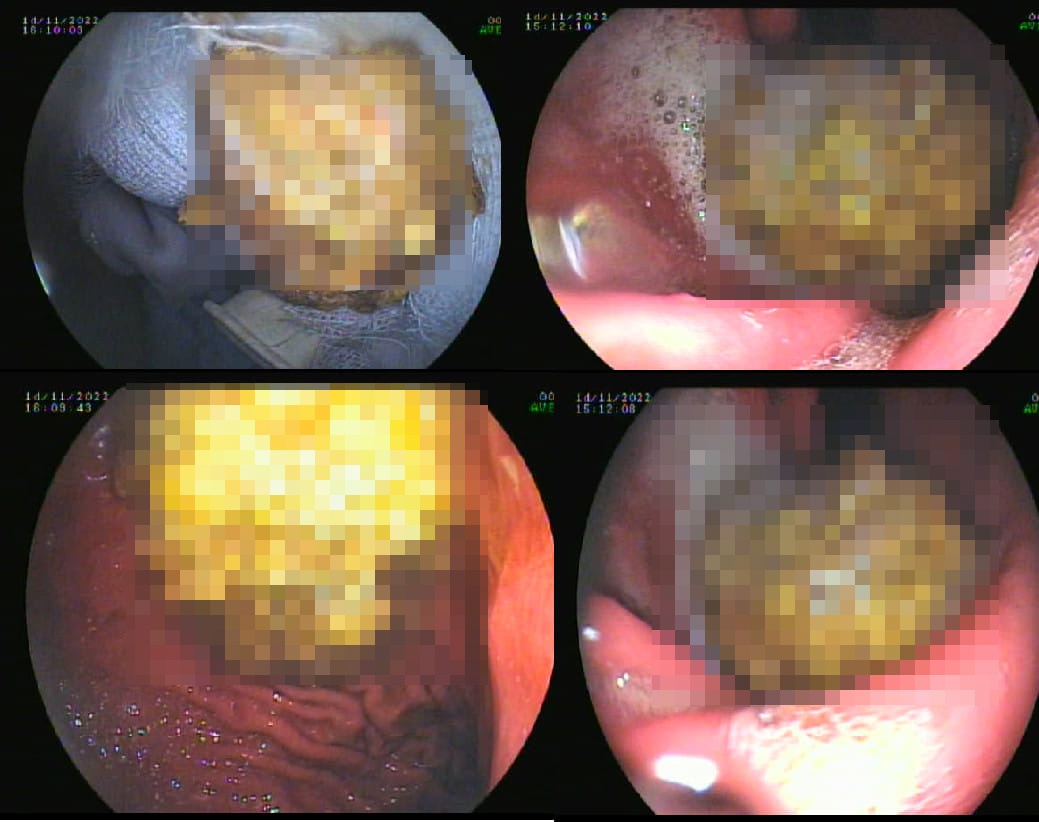

Trong quá trình nội soi, các bác sĩ phát hiện khối bã thức ăn lớn trong dạ dày, gây viêm xuất huyết niêm mạc.

Qua tìm hiểu, trước đó, bệnh nhân đã mua một kg hồng giòn về nhà ăn. Tại bệnh viện, bệnh nhân được chỉ định nội soi dạ dày. Lúc này, các bác sĩ bất ngờ phát hiện khối bã thức ăn lớn, kích thước 3x5 cm nằm trong dạ dày của bệnh nhân.

Khối bã thức ăn này tạo thành khối màu trắng ngà, cứng chắc, gây viêm xuất huyết niêm mạc dạ dày.

Khối bã thức ăn được lấy ra từ dạ dày của bệnh nhân. Ảnh: BVCC.

Theo bác sĩ Vương Khả Vinh, Phó trưởng khoa Chẩn đoán hình ảnh, ê-kíp nội soi đã lấy khối bã thức ăn qua nội soi mềm bằng cách cắt thành nhiều miếng nhỏ, sau đó đưa ra ngoài thông qua đường miệng.

Sau hơn một giờ, toàn bộ khối bã thức ăn mới được lấy ra ngoài. Bệnh nhân hồi phục sức khỏe, ăn uống bình thường trở lại vào ngày hôm sau.